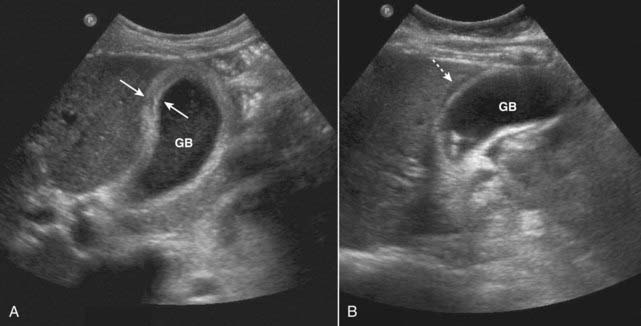

Figure 19-5 Acute cholecystitis, sagittal views, two patients.

A, Thickening of gallbladder (GB) wall. The wall should be 3 mm or less. This wall is markedly thickened at 6 mm (solid white arrows). B, There is an echo-free crescent (dotted white arrow) surrounding a thickened gallbladder (GB) wall representing pericholecystic fluid. The patient had a positive sonographic Murphy sign.